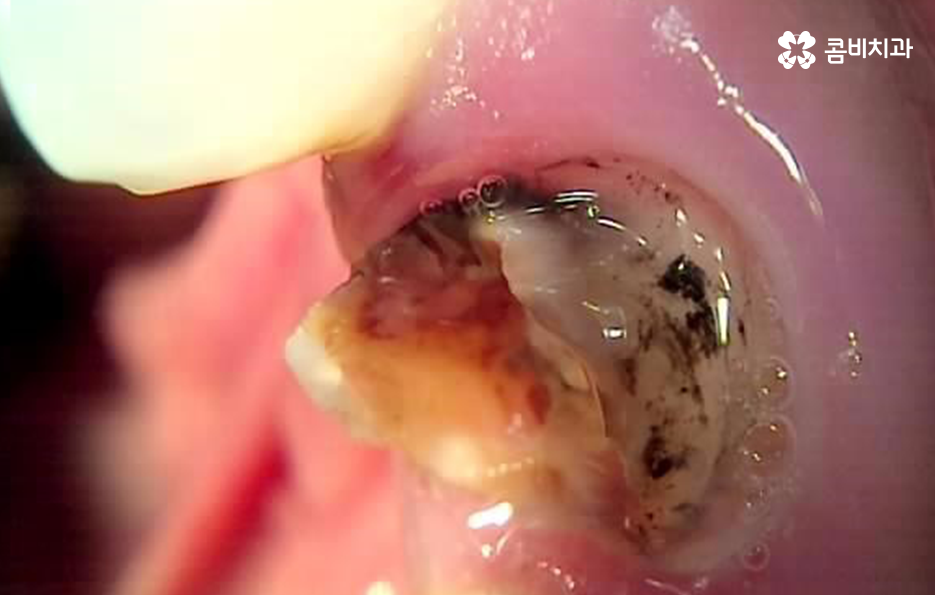

하지만 성인들의 충치 치료는 위 사례들처럼 과거 오래전에 치료 했던 아말감이나 보철물이 떨어지기도 하고 접착제가 약해지면서 2차 충치가 내부에서 진행되어 보철물을 제거하고 내부 상태를 파악해야 하는 경우가 자주 발생되고 있는데요

크고 작은 보철치료를 하다 보면 보철물의 수명이 다하고 교체를 해야하는 시점이 찾아오게 되는데 보철물 내부에서 발생될 수 있는 2차 충치는 기본적으로 주기적으로 검진하지 않고 통증이나 특정 불편함으로 인해 치과에 방문하게 되시면 치료의 적기를 놓치는 경우가 많다고 볼 수 있어요

또한 치료는 보기 좋게 레진으로 교체 치료가 가능하다고 해도 어금니 처럼 압력을 강하게 받는 치아 부위의 경우 혹은 치아의 홈 부분이 아니라 옆면 치료를 해야 하는 경우에는 당장의 치료 결과만이 아니라 치료 후 유지와 지속성에 대해서도 고려해야 하기 때문에 레진으로 치료가 가능하더라도 금방 레진이 깨지거나 탈락우려가 높다면 인레이 치료나 크라운 치료를 하게 되는 경우가 발생될 수 있어요